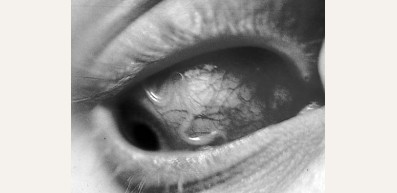

Педикулез (вши)

Педикулез. Причины, симптомы и признаки, средства для лечения патологии, профилактика